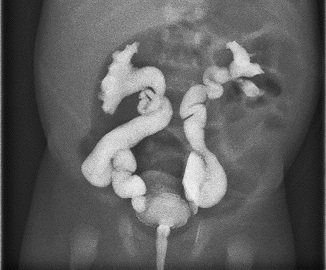

【112-2 醫學(五) 第46題】2個月大男嬰因發高燒入院治療,檢查發現泌尿道感染合併菌血症及腦膜炎,經抗生素治療3天後發燒逐漸緩解,腎臟超音波發現兩側水腎,遂安排voiding cystourethrogram,檢查結果如圖所示,應診斷為:

詳解

破題關鍵

這題的關鍵是判讀膀胱輸尿管逆流(Vesicoureteral Reflux, VUR)的影像分級。圖片顯示顯影劑從膀胱嚴重逆流至雙側輸尿管及腎盂腎盞,且有明顯的輸尿管擴張、扭曲及腎盞變鈍(clubbing)。